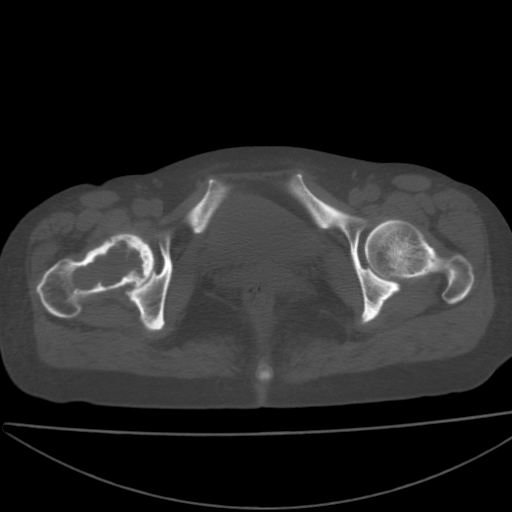

以下是引用xiaoniu在2008-9-6 8:22:00的发言:[br]右侧股骨颈囊性低密度,囊壁边缘硬化,中年妇女,首先考虑:骨囊肿。其次考虑动脉瘤样骨囊肿。[br][br][br][本贴已被 xiaoniu 于 2008-9-6 9:04:54 修改过]